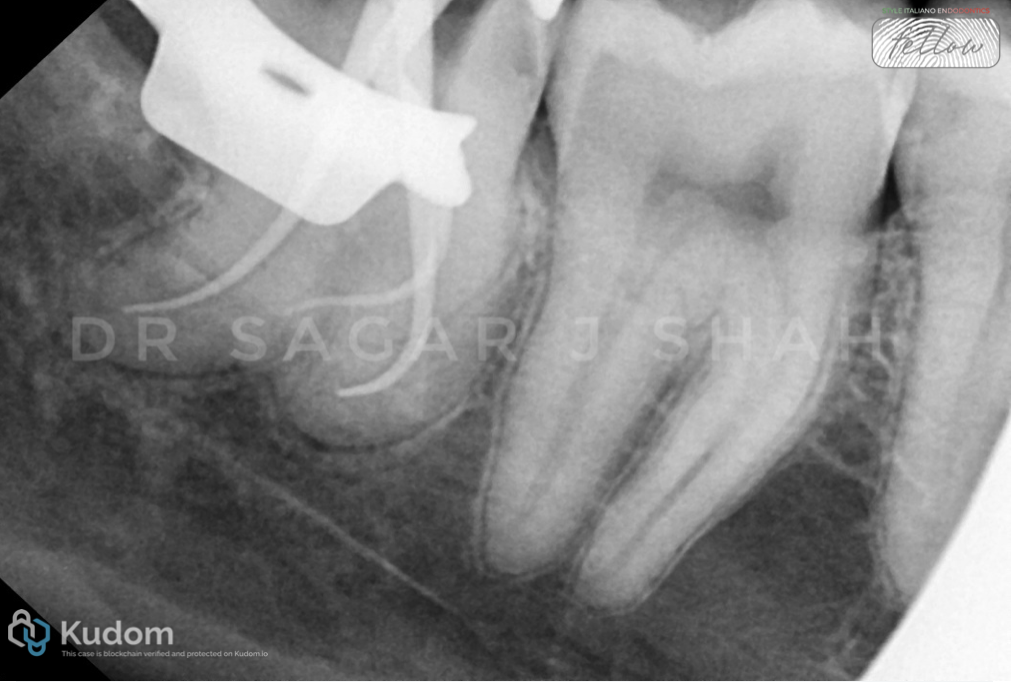

PREOPERATIVE ASSESSMENT:

Mesial canal curvature- 60 degree

Distal canal curvature- 30 degree

The radius of curvature- 14 mm

Close proximity to the mandibular canal.

Pulp calcification was seen with the distal root.

AAE DIFFICULTY ASSESSMENT- HIGH